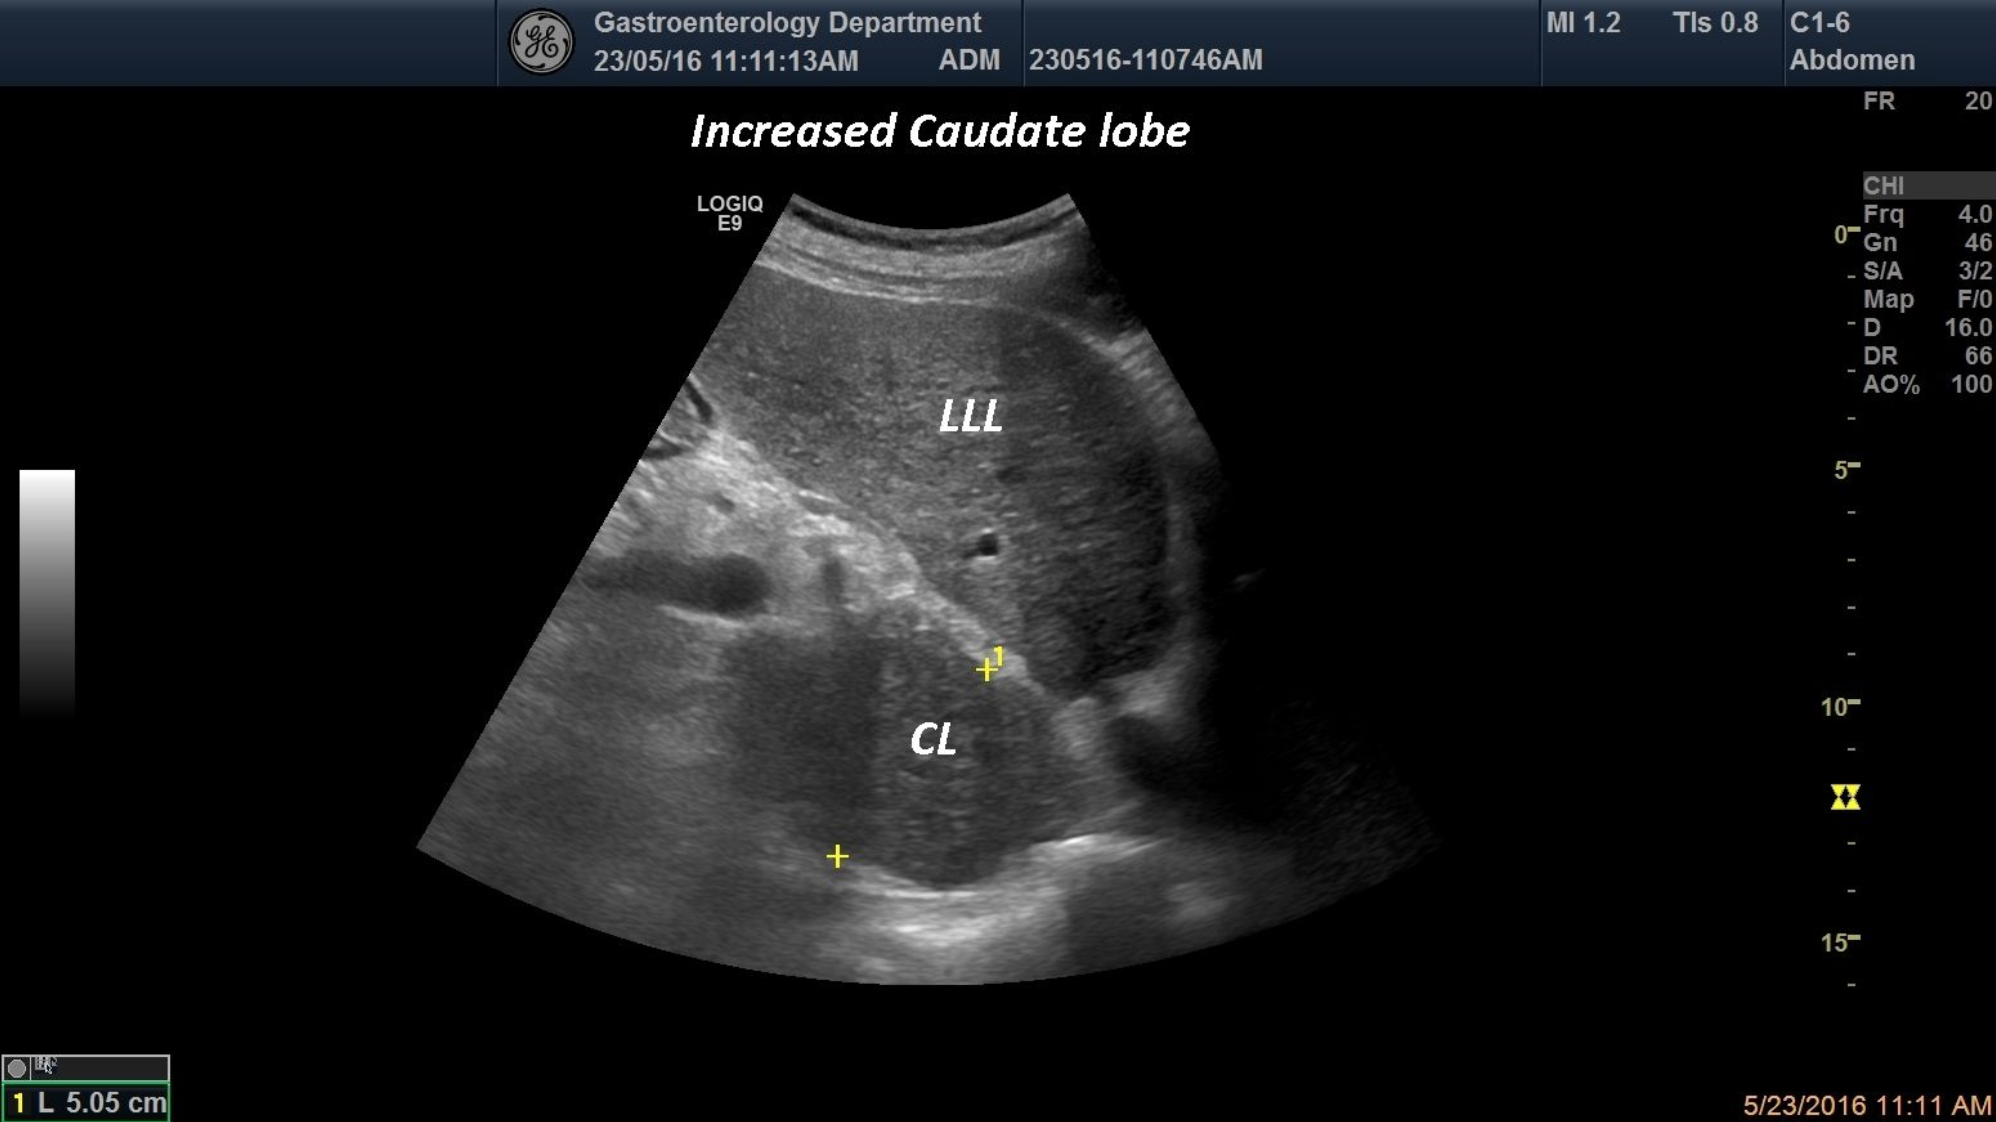

TITLE: Increased caudate lobe

A patient was referred to the Gastroenterology department for an ultrasound evaluation. We depicted an increased caudate lobe. The diagnosis of advance liver fibrosis was confirmed after an elastographic method was performed.

caudate lobe, liver fibrosis, anechoic structure